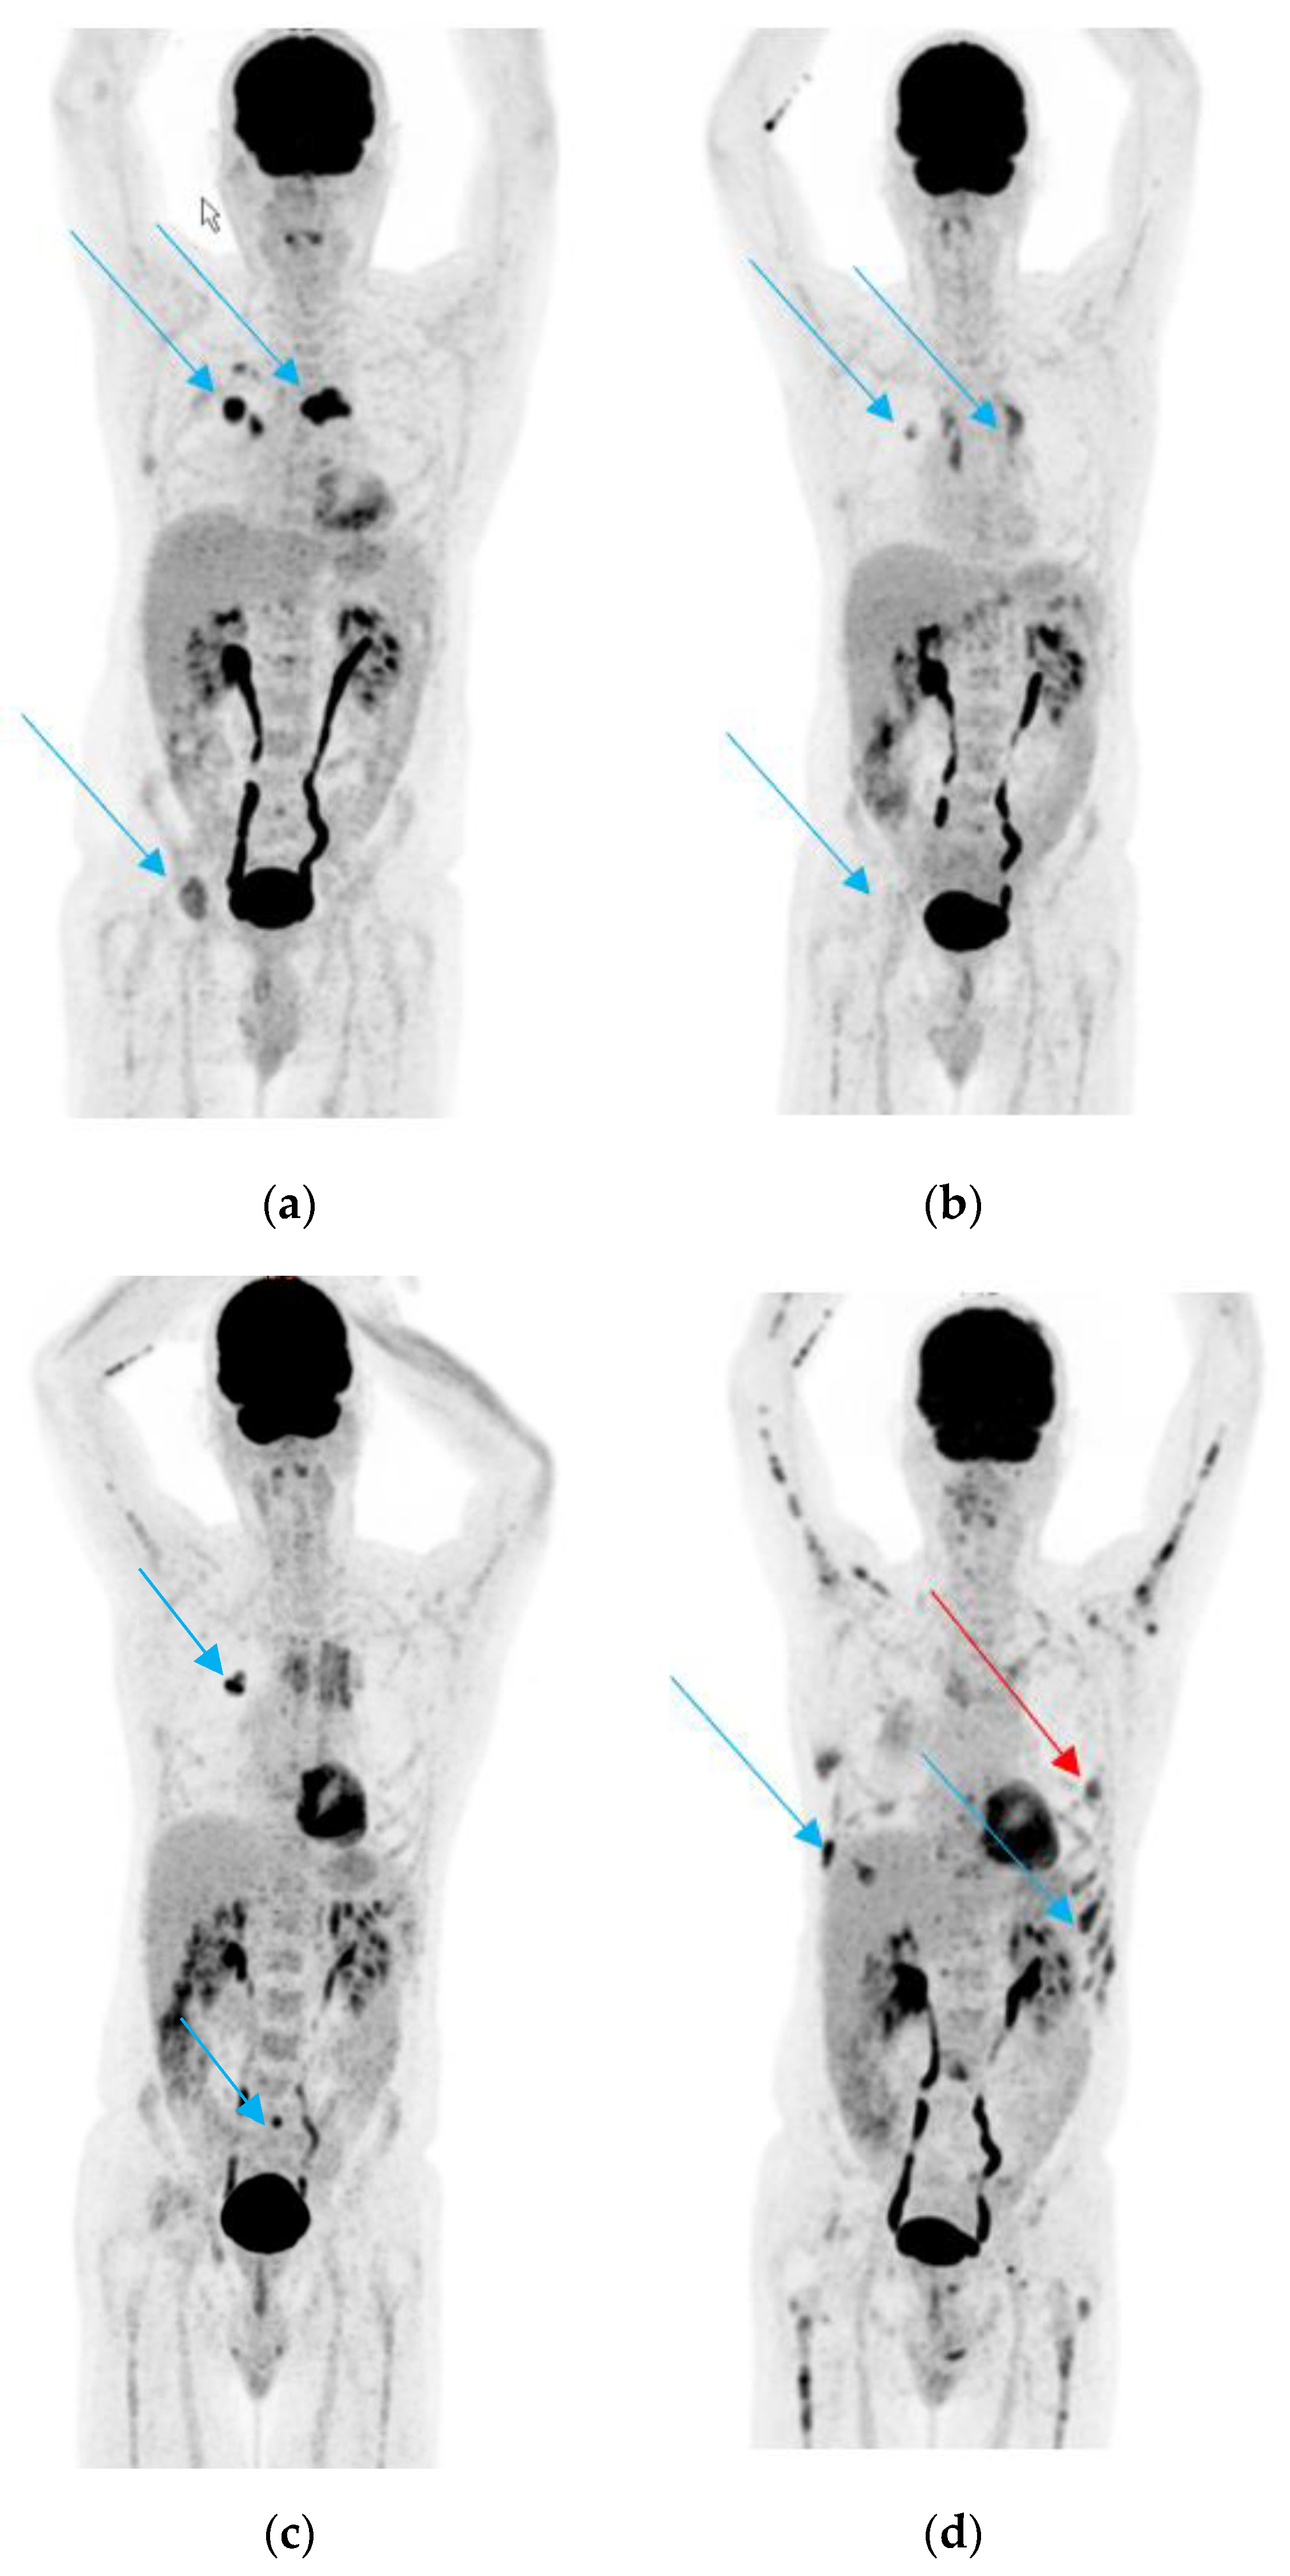

3.1. Case 1

3.2. Case 2

3.3. Case 3